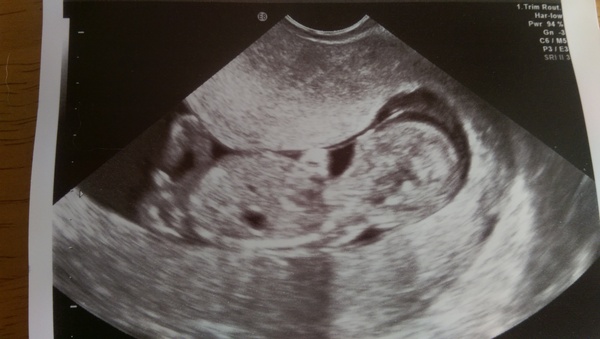

My scan went well, although it seems we have either a sleepy child (takes after DP) or a moody one (takes after me). Baby was obviously being uber optimistic, and was lying in the birthing position - head down, facing my back. It was so low down in my pelvis that the sonographer couldn't get a proper view of the head. So, after a thankful run to the loo, I ended up having an internal scan.

We got great views, although whilst the sonographer was cooing, "And there's a hand, and there's an arm, and there's the bladder...", I was thinking, "There's a blob, there's a longer blob, there's a black blob...". We did see the cross section of the brain, and a freaky alien-esque view of the eyes (I believe viewed from the back of the head). Also saw one mahoosive foot, which appeared larger than the head and I'm putting down to an odd perspective (DP is putting it down the the baby taking after me!).

I also gained my day back that day I lost, so am 12+6 again now. Baby seems to have all the right bits, had HR of 164, wiggled legs like crazy, but...and this was the problem...flatly refused even a sideways glance at the camera. Regardless of any amount of coughing, prodding and poking my belly (and, rather alarmingly to me) having the dildo cam wiggled rapidly inside me

all we got was a view of the back of the head.

So, I was unable to have the combined screening, and am going back in 12 days to have the quadruple blood test instead. She did say that she was happy with what she could see that there was no thickening of the neck, but she couldn't get an accurate measurement for the test.

I'll post up a pick of stroppy baby refusing to look at camera in a mo.